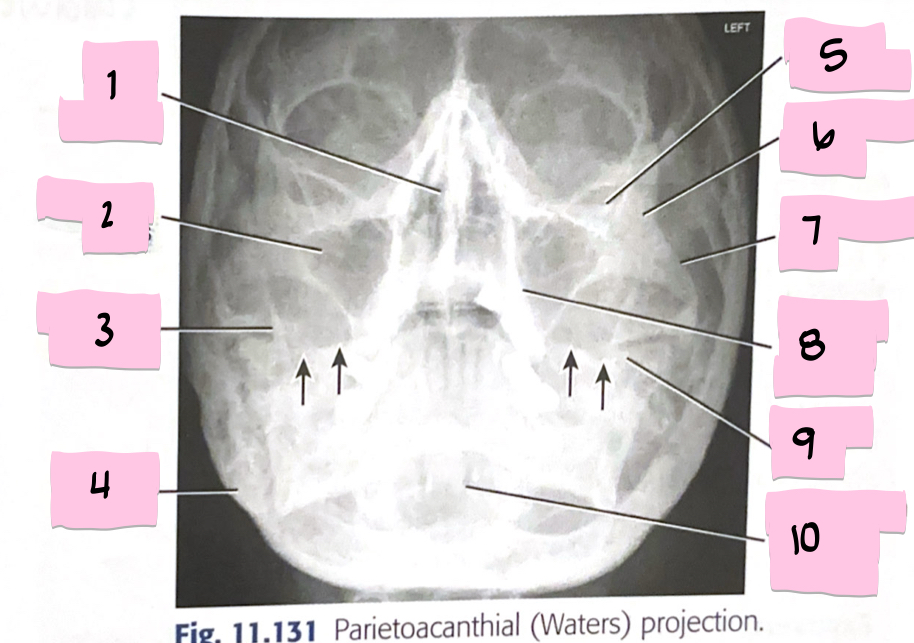

What is 1 pointing to?

Frontal sinus

What is 2 pointing to?

Superior orbital fissure

What is 3 pointing to?

Bony nasal septum

What is 4 pointing to?

Anterior nasal spine

What is 5 pointing to?

Crista galli

What is 6 pointing to?

Petrous ridge

What is 7 pointing to?

Floor of orbit

What is 8 pointing to?

Maxillary sinus